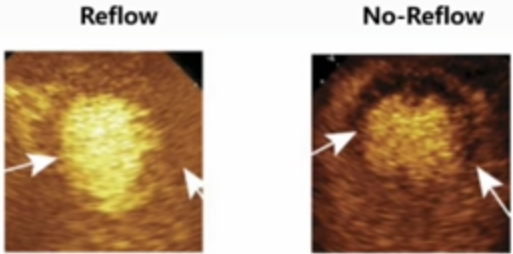

无复流的评价方法:从血流恢复到心肌灌注。

心肌呈色分级(MBG): 反映心肌组织灌注和对碘对比剂清除情况,分0-3级,其中0-1级定义为无复流;在TIMI 3级惠者中,有50%左右MBG为0-1级。

定义“TIMI< 3级且TFC>40 或 TIMI 3级时MBG 01级”为无复流,较单纯TIMI分级更准确。